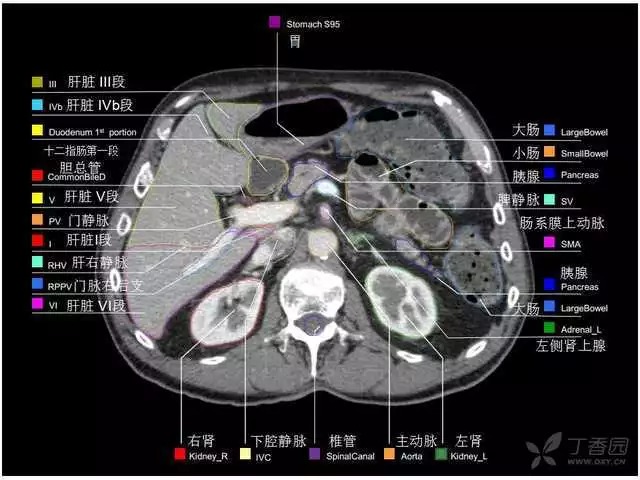

腹部肝脏高清CT断层的图谱

全腹部高清CT图谱,淋巴结彩色图谱,血管解剖图谱大汇总!

超声肝脏分叶及分段

肝脏分段和基本解剖学标志